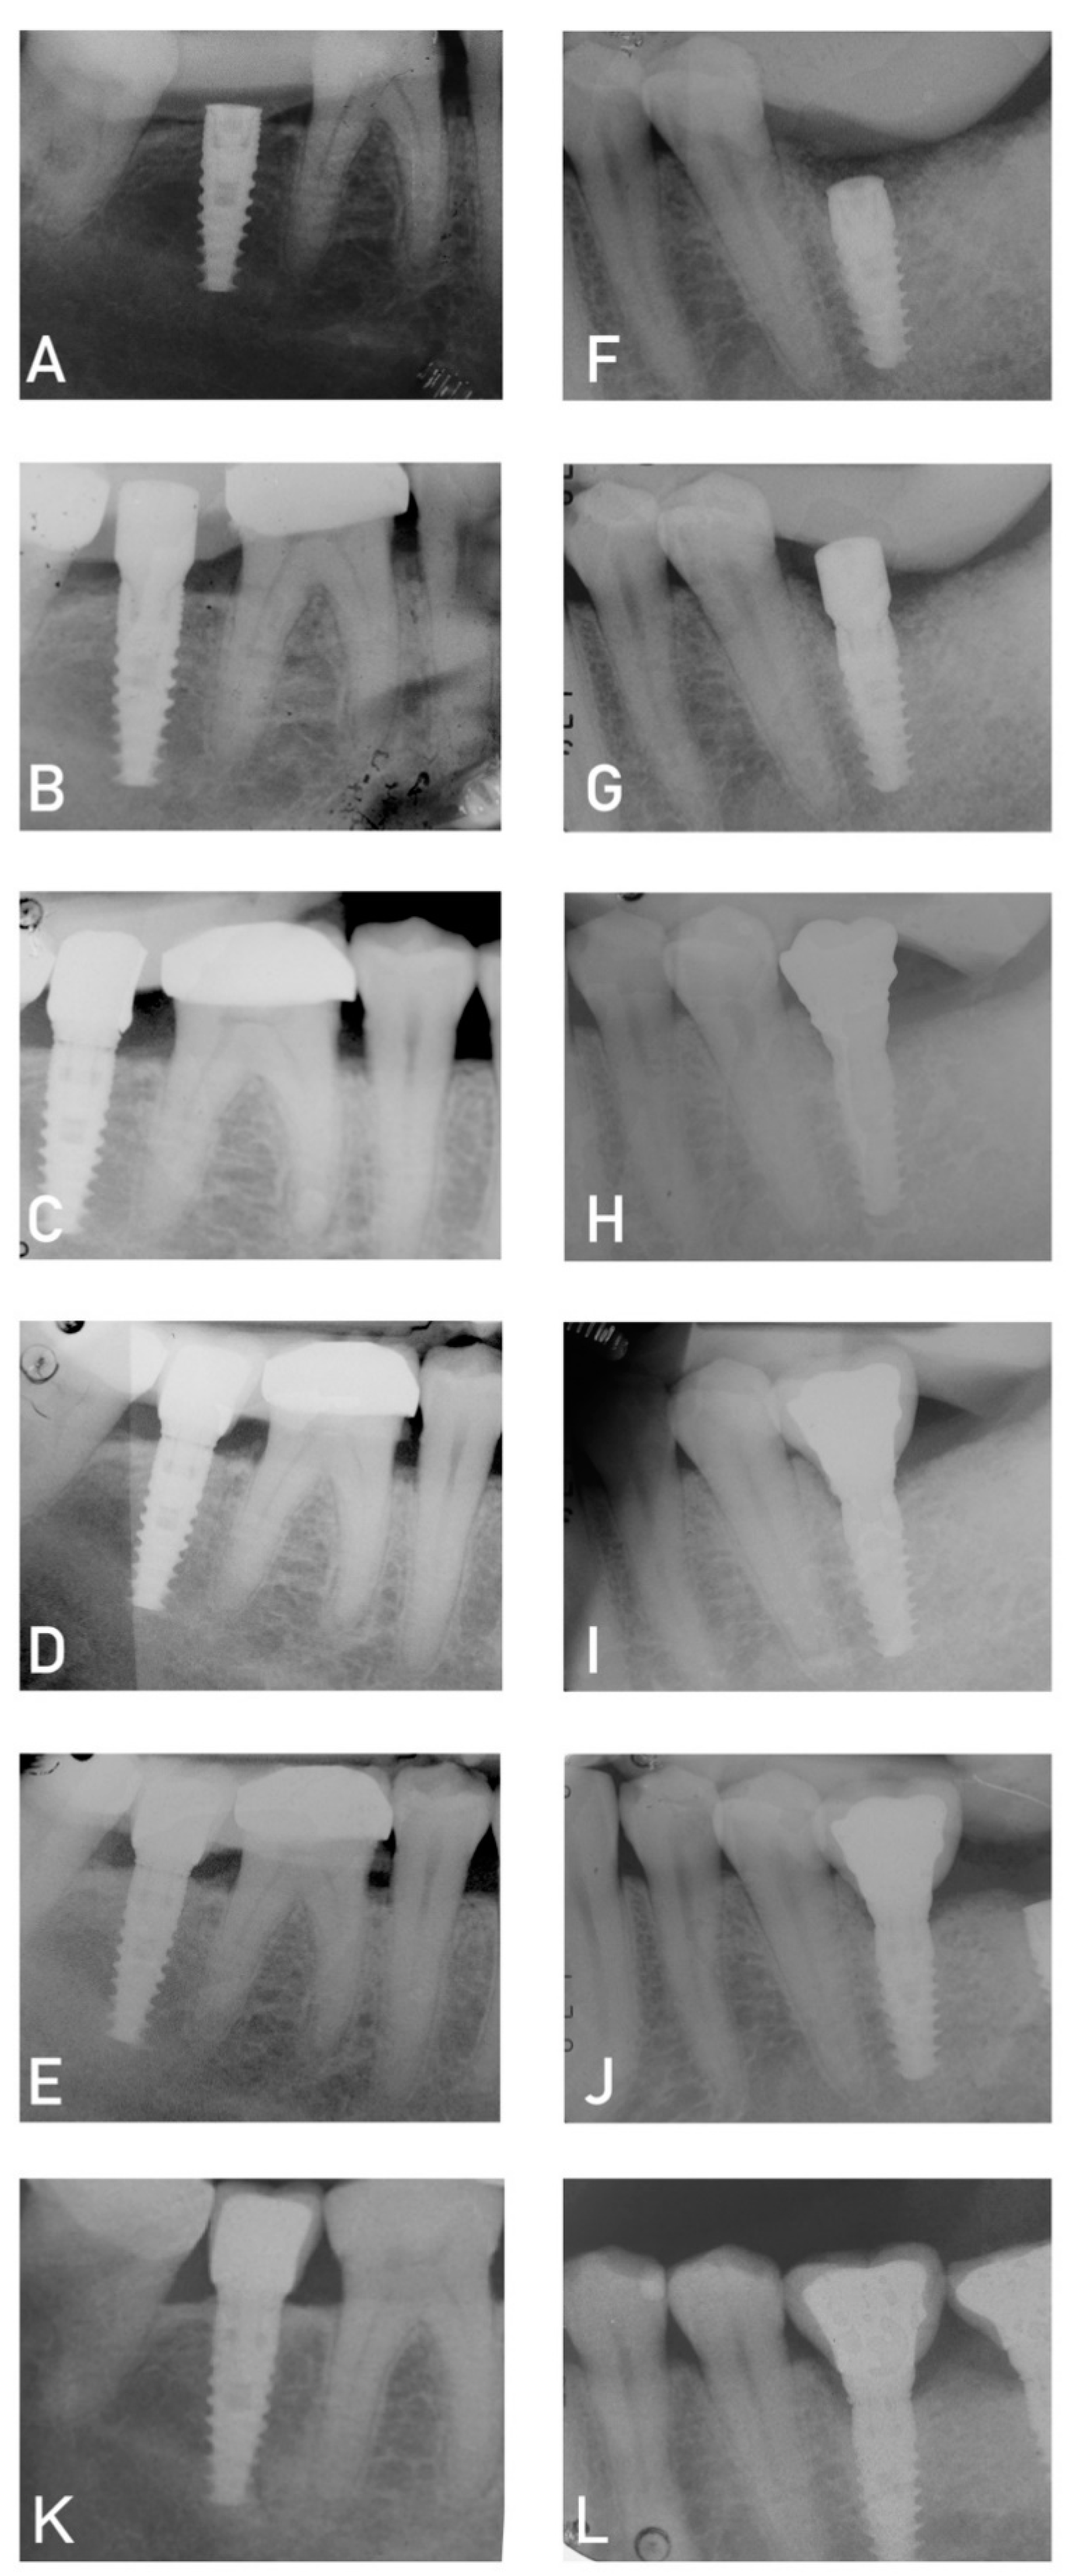

- Periapical X-ray